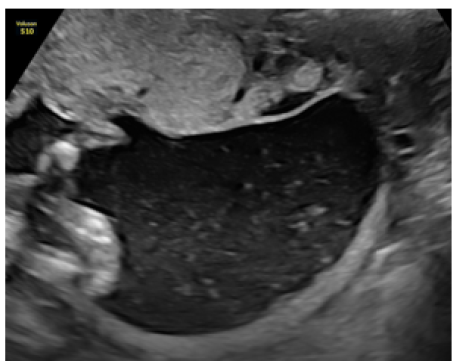

Prenatal Diagnosis of Aplasia Cutis Congenita on the Superior and Inferior Limbs with 2D Ultrasound: Case Report

Kariman Ghazal MD, Mira Hdeib MD, Imad Abou Jaoude MD and Jihad El Hassan. 12(1): 90-96.